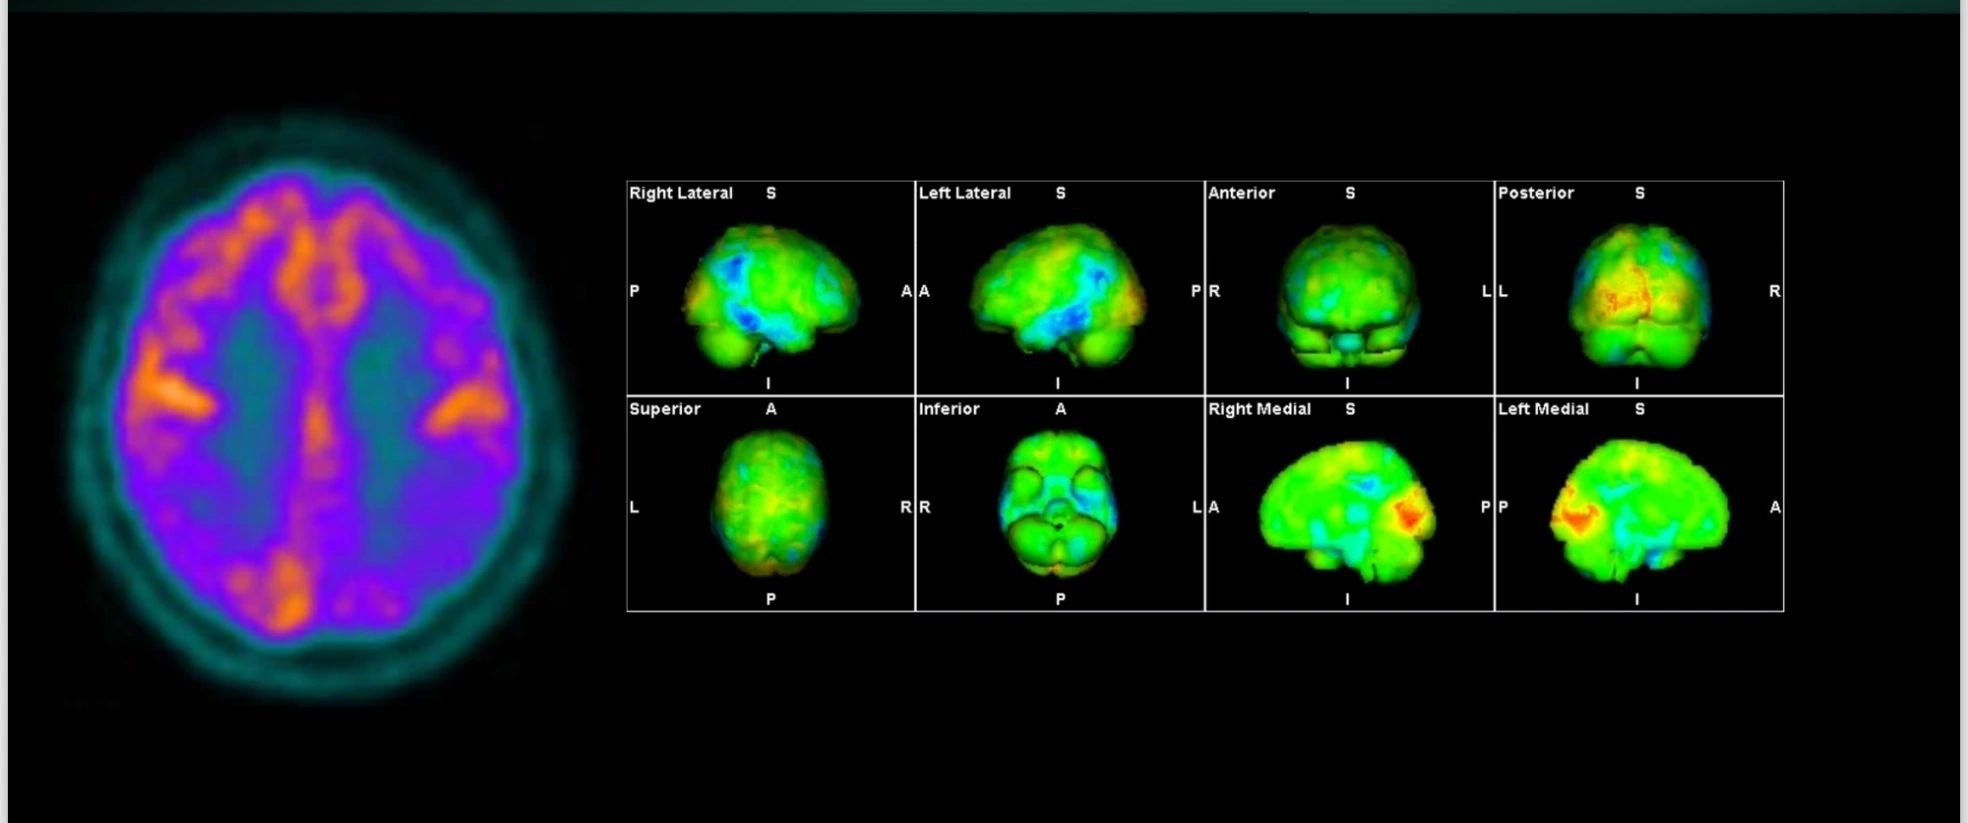

Η Τομογραφία Εκπομπής Ποζιτρονίων (PET) αποτελεί μια εξειδικευμένη μέθοδο της Πυρηνικής Ιατρικής που χρησιμοποιεί μοριακή απεικόνιση για να εντοπίσει και να παρακολουθήσει φυσιολογικές και παθολογικές λειτουργίες του οργανισμού. Συνδυάζοντας τη λειτουργική απεικόνιση της PET με την ανατομική πληροφορία της αξονικής τομογραφίας (CT), η υβριδική εξέταση PET/CT παρέχει εικόνες υψηλής ευκρίνειας και τη δυνατότητα ποσοτικής αξιολόγησης των βιολογικών μηχανισμών σε κυτταρικό επίπεδο.

Οι κυριότερες εφαρμογές της αφορούν την ογκολογία, τη νευρολογία και, σε μικρότερο βαθμό, την καρδιολογία, ενώ συνεχώς αναπτύσσονται νέες χρήσεις σε άλλες ιατρικές ειδικότητες.

Στο Κέντρο PET/CT πραγματοποιούνται εξειδικευμένες εξετάσεις που καλύπτουν ένα ευρύ φάσμα κλινικών εφαρμογών στη σύγχρονη Πυρηνική Ιατρική. Ανάλογα με το είδος του προβλήματος και τη φύση της νόσου, χρησιμοποιούνται διαφορετικά ραδιοφάρμακα για τη μελέτη συγκεκριμένων βιολογικών μηχανισμών.